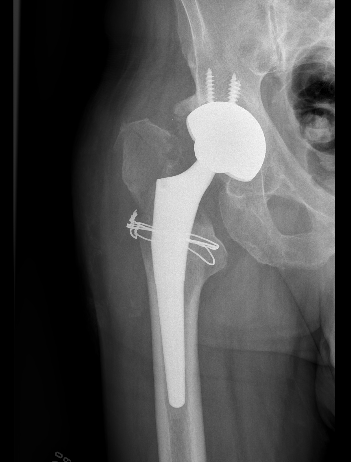

Dislocated constrained liner

Successful reduction constrained liner

Unsuccessful reduction constrained liner